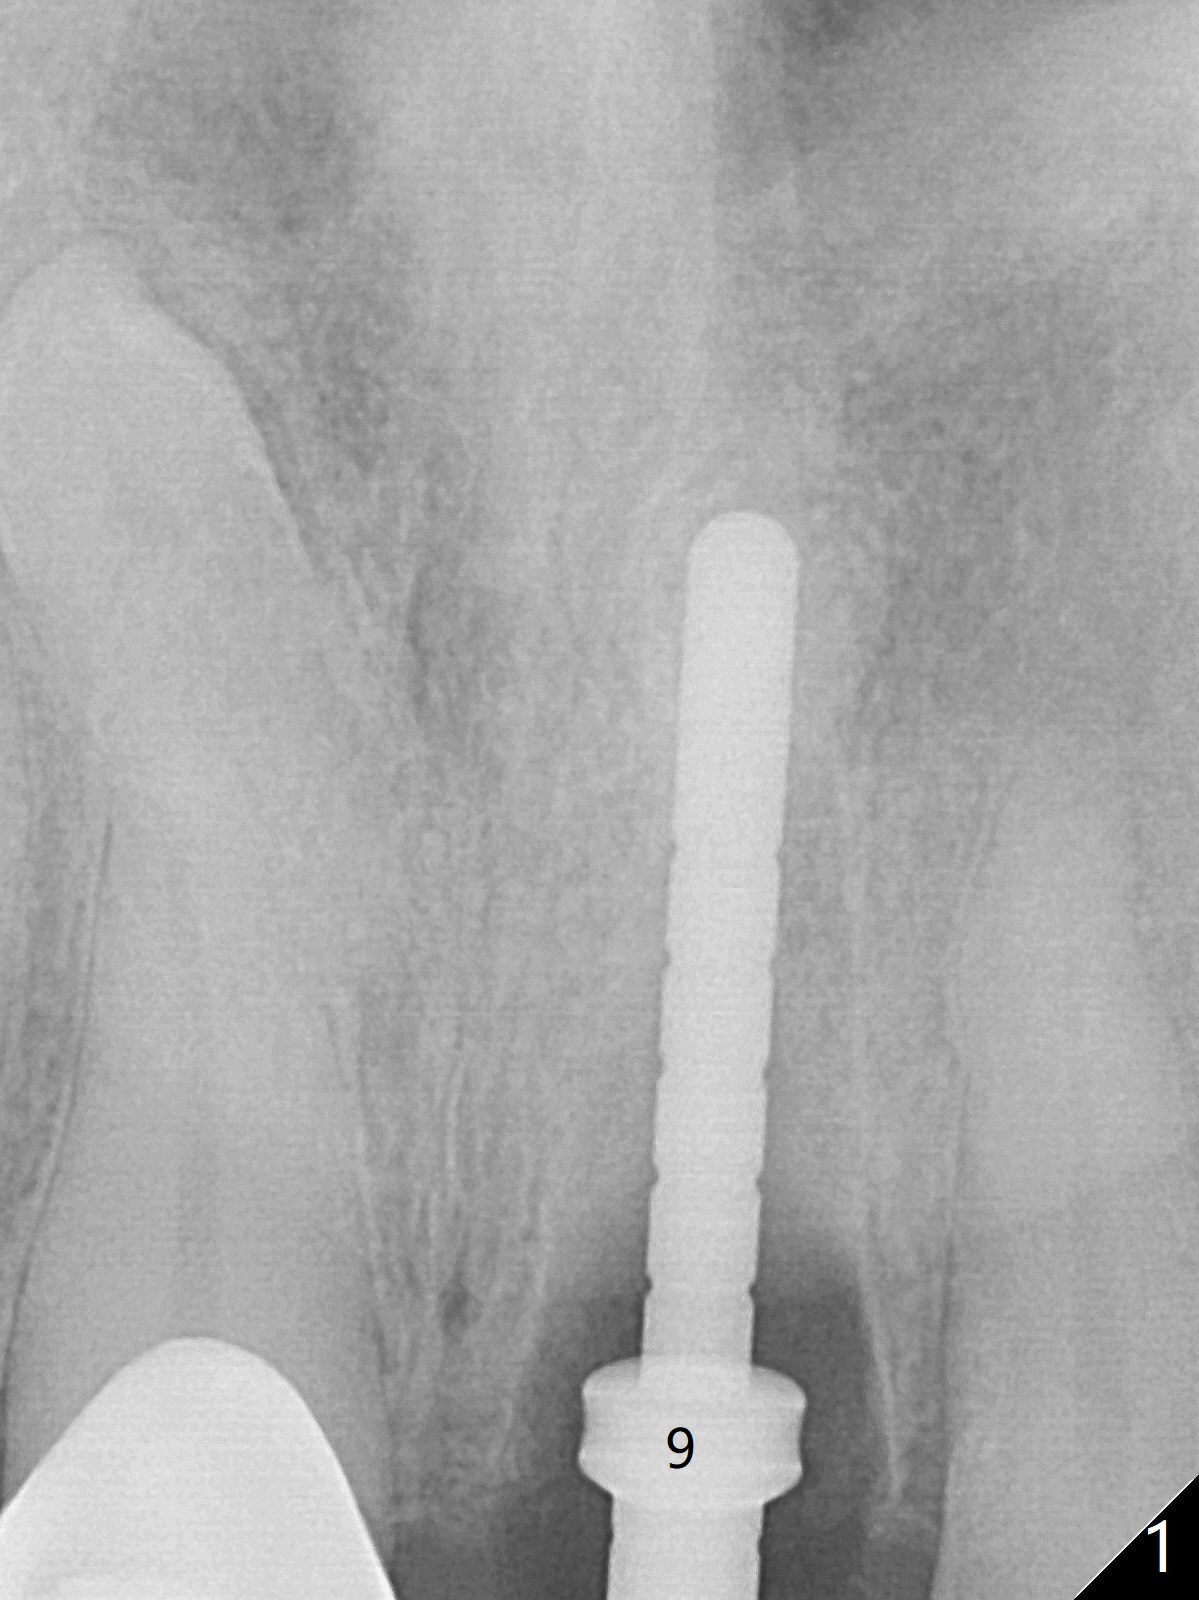

The buccal plate at #9 remains intact in spite of difficult extraction. Osteotomy is initiated in the palatal slope of the socket (Fig.1). The latter looks large when osteotomy is finished for a 3.8 mm implant. Without further osteotomy, a 4.5x14 mm SM implant is placed with primary stability (Fig.2). Without much attention, the coronal end of the bone-level implant is gradually deviated buccal, although the buccal gap is still 2 mm. An angled abutment is used (Fig.2); the future access hole is also buccal. Screw retention is impossible for cosmetic reason (Fig.3). To keep the access incisal and palatal, keep removing palatal bone sequentially. Or start osteotomy in the mid point of the palatal slope and keep the coronal end of the trajectory (Fig.5 pink line) palatal to the imagined incisal edge (Fig.4 white outline). The implant should be small (3.5 mm instead of 4.5 mm) so that it is easy to change the trajectory. The bone graft seems to have disappeared 3.5 months postop; the implant appears to have not been placed deep enough (Fig.6). In fact the implant plateau is < 2 mm subgingival palatal. An anterior immediate implant should be placed deep to reduce periimplantitis. There is reduced risk associated with abutment screw loosening, as compared to the posterior. Luckily the patient has used water pik since implant placement. On the other hand, water pik may be related to loss of bone graft. Therefore, water pik should be used 1 month post bone graft associated with immediate implant. The bone graft remains around the abutment cuff 4 months postop (Fig.7; immediately post cementation).